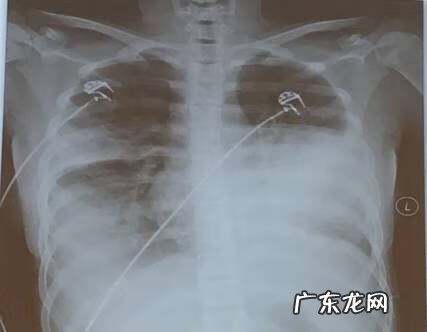

文章插图

两肺大片状致密影,左心缘显示不清,双膈面模糊,左侧胸壁可见弧形致密影 。